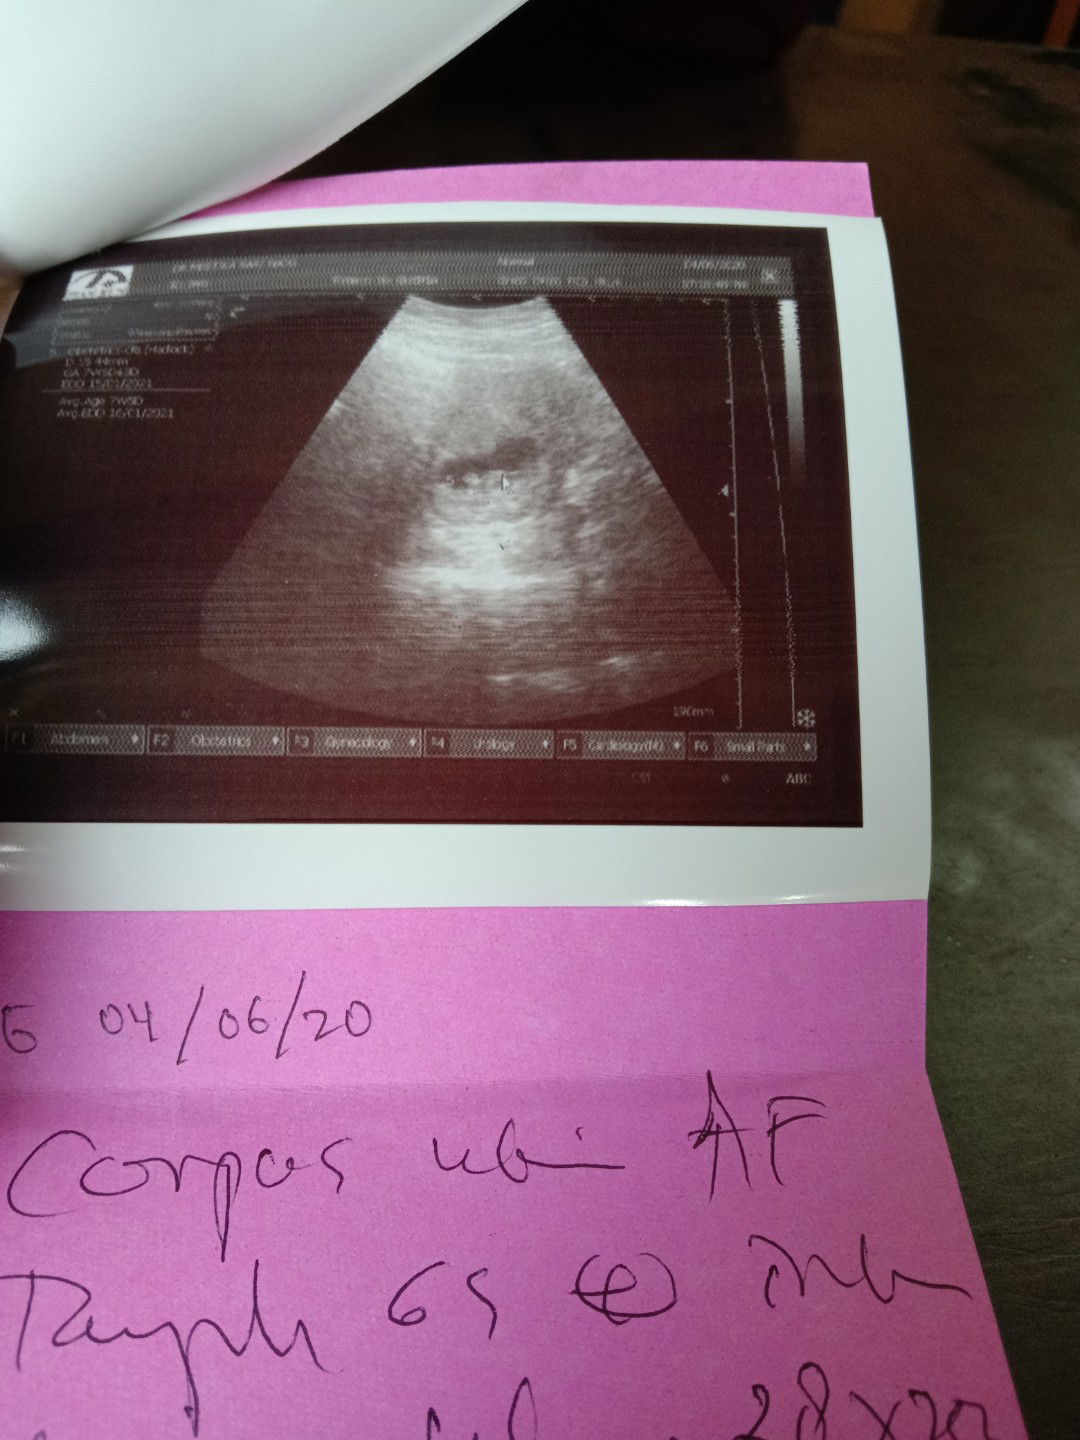

USG pertama

Menurut hpht udah 8w3d ,tp d usg 7w6d selisih dikit aja.. Alhamdulillah bayi nya ada di dalam rahim ,normal semua. Semoga kta yg sedang hamil di mudah kn sampai lahiran , buat yg lagi berjuang garis 2 ,semoga Allah segera kan... Allahumma aamiin.